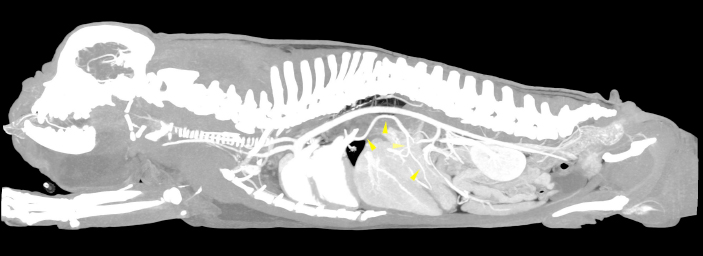

A 5-year-old male French Bulldog of 13 kg was referred to our diagnostic center because of the presence of a voluminous swelling in correspondence of the intermandibular region, with a first suspect of a neoplastic lesion and less probably a severe sialocele. In the previous 2 weeks, the patient underwent a non-specified antimicrobial and anti-inflammatory therapy without significant improvements. The remote pathological anamnesis was silent. The anamnestic and clinical examination revealed depression, anorexia, severe breathing difficulty, abundant respiratory secretions and hyperthermia (39.8°C). Complete blood cell count (IDEXX ProCyte DxTM) indicated monocytosis (1.49 K/μl, range 0.16–1.12 K/μl), thrombocytopenia (64 K/μl, range 148–484 K/μl) and mild/moderate normocytic and normochromic non-regenerative anemia (RBC 4.53 M/μl, range 5.65–8.87 M/μl; HCT 28.0%, range 37.3%–61.7%, HGB 9.8 g/dl, range 13.1–20.5 g/dl), in first hypothesis indicating a chronic inflammatory disease. All biochemical parameters examined (IDEXX Catalyst OneTM), in particular alkaline phosphatase (ALP), gamma-glutamyl transferase (GGT), alanine aminotransferase (ALT), cholesterol, triglycerides, bilirubin, creatinine, urea and albumin were within normal limits, except for a mild increase in total proteins (10.0 g/dl, range 5.2–8.2 g/dl) and in globulin (7.7 g/dl, range 2.5–4.5 g/dl). The same day, the dog underwent a total-body CTA examination under general anesthesia, that was performed using a 16-slice scanner (GE Healthcare Optima CT520) with a slice thickness of 0.625 mm, 120 kW, 150 mA and a pitch < 1. The patient was positioned in sternal recumbency, and the image acquisition was carried out in the native scan phase and after about 40 seconds from the injection of 2 mg/kg iodinate contrast medium (Iopamiro, Iopamidolo 370 mgI/ml) followed by 1 mg/kg bolus of physiological solution (0.9% NaCl). Images were reformatted using bone and soft tissue algorithms. The CTA examination showed the presence of an anomalous vascular connection between the PV and the lobar vein of the caudal left pulmonary lobe. This anomalous vessel originated from the ventral aspect of the PV, cranially to the portal entering of the gastroduodenal vein. The vase went caudo-ventrally along the small gastric curvature, and subsequently dorso-cranially towards the esophageal hiatus, receiving two branches of the left gastric vein. At the hiatus, the shunt rotated dorsally around and in contact with the cardias, from the median line to the left side of the dog. Afterwards, the vessel entered the lobar vein of the caudal left pulmonary lobe, 1.1 cm before its entry into the left atrium (Figs. 1 and 2). The porto-pulmonary shunt showed an almost constant diameter, starting from 2.0 mm at its origin in correspondence of the PV, increasing to 2.6 mm at the level of the esophageal hiatus and 3.4 mm before entering the left lobar pulmonary vein. The diameter of the PV was 6.8 mm at the porta hepatis, while it was 7.8 mm before the origin of the anomalous vase. Neither hepatic lesions nor intraparenchymal portal vascular texture anomalies were observed, and the hepatic volume was within normal limits. No other shunts, varices, peritoneal effusion or CTA-perceived cardiac abnormalities were detected. No nephromegaly, based on renal length-to-aorta diameter (Hoey et al., 2016), was observed. The dog also underwent an echocardiographic and an abdominal ultrasound examination, performed by an experienced radiologist, without evidences of functional or morphological abnormalities. The final clinical diagnosis consisted of a severe infected sialocele sustained by Fusobacterium necrophorum isolated by cultural examination and the presence of the porto-pulmonary shunt was interpreted as an incidental finding. The patient died the following day because of respiratory failure and the owner did not allow the necropsy.

Fig. 1. Sagittal MIP view of the venous phase. The yellow arrowheads indicate the anomalous vessel connecting the portal system with the lobar vein of the caudal left pulmonary lobe.